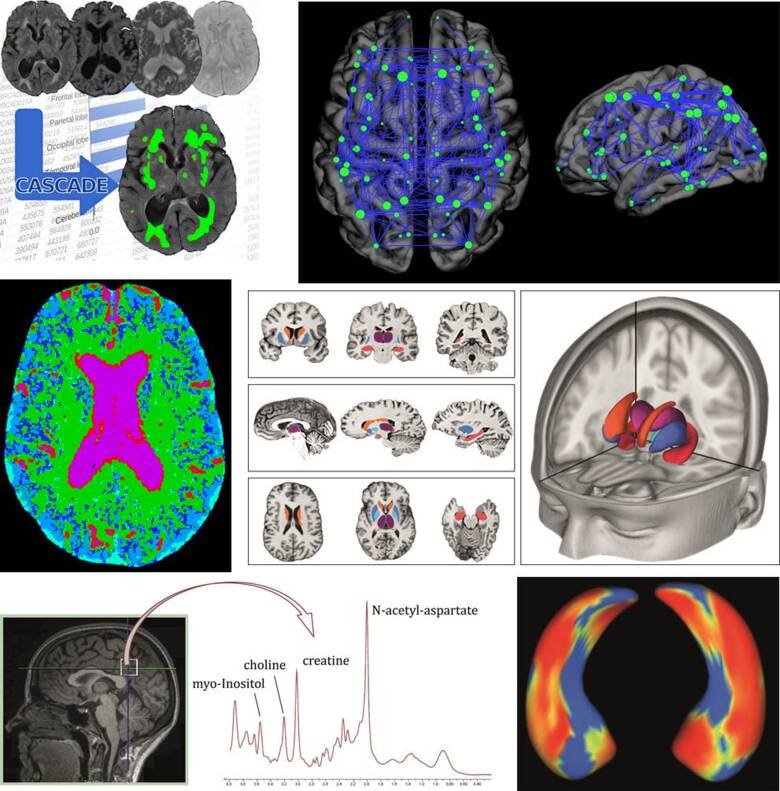

Stor vikt läggs vid strukturell och funktionell hjärnavbildning för att förstå de bakomliggande mekanismerna för olika demenssjukdomar, vilket förhoppningsvis kommer leda till säkrare diagnostik. Vi har ett starkt fokus på olika magnetresonanstomografi (MRT) tekniker och använder även andra metoder i vår forskning så som positronemissionstomografi (PET) och datortomografi (DT).

Avancerade verktyg (multivariata metoder, maskininlärning och grafteori) används för att analysera de stora mängder data som de olika bildgivande metoderna ger. För närvarande är en stor del av forskningen inom gruppen inriktad på att förstå heterogeniteten inom AD samt att förstå hur de olika demenssjukdomarna relaterar till varandra. Vi tycker att det är viktigt att arbeta med de senaste hjärnavbildningsteknikerna för att få en bättre förståelse för de olika sjukdomarnas underliggande mekanismer, för att förbättra tidig diagnostik och differentialdiagnostik.